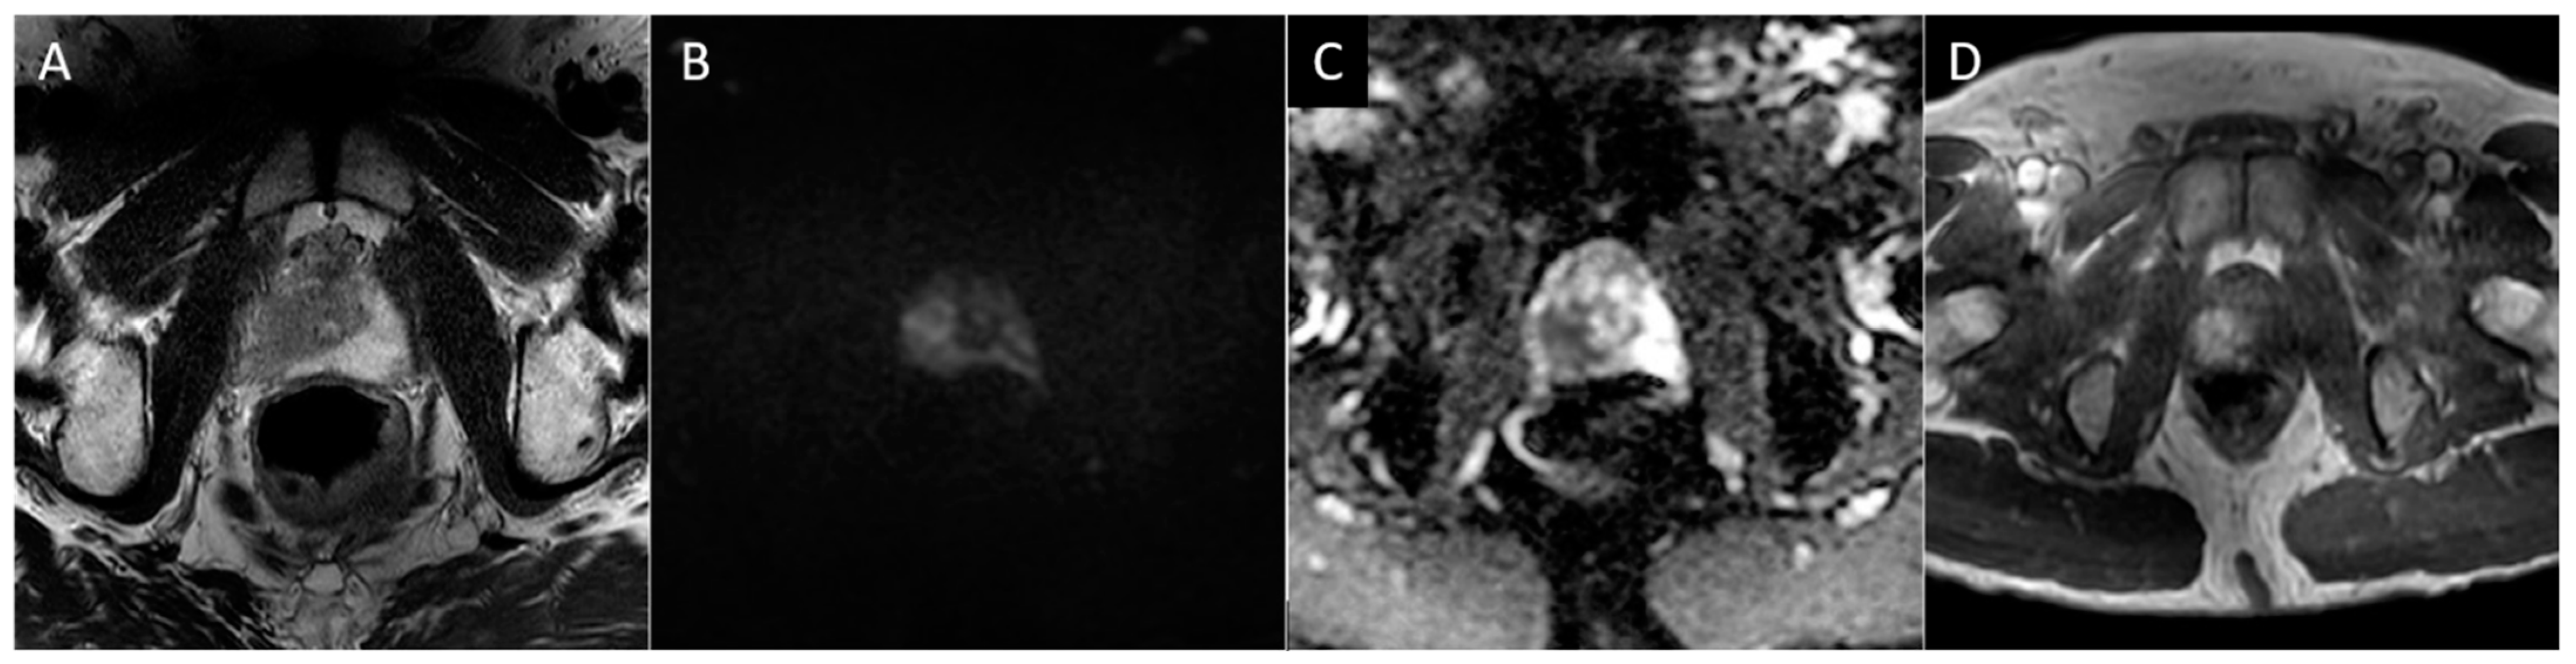

Figure 2. Axial T2 (A), diffusion-weighted b2000 (B), apparent diffusion coefficient (C), and dynamic contrast-enhanced (D) images of the pelvis demonstrating a focal ill-defined T2 hypointense lesion in the right midgland posterolateral peripheral zone with corresponding diffusion restriction and asymmetric enhancement, characterized as PI-RADS 5 per PI-RADS v2.1.